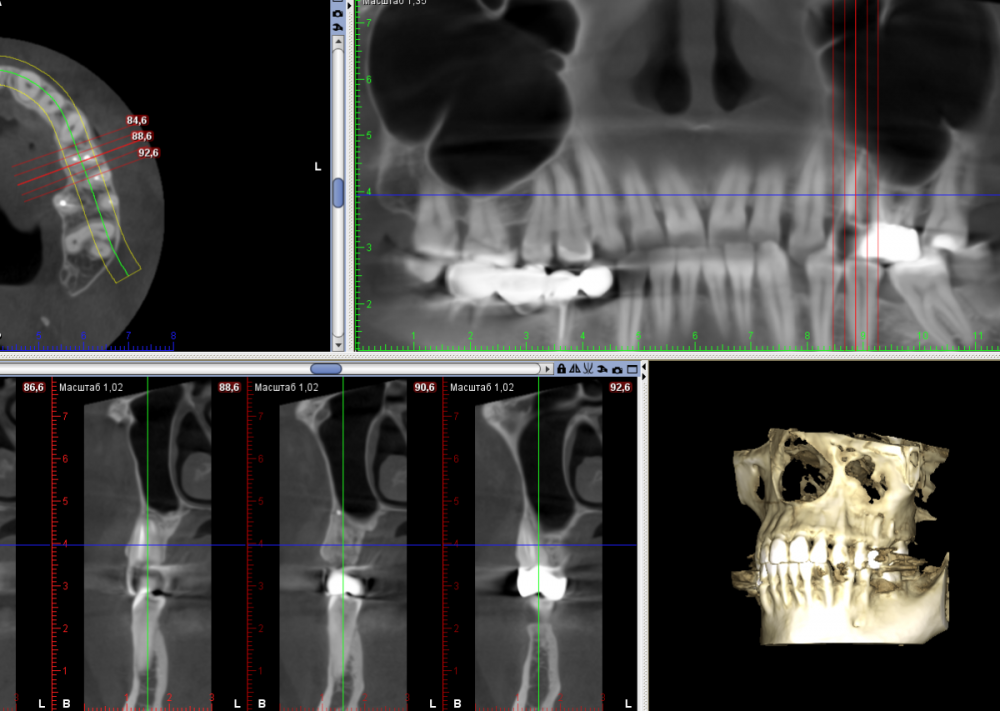

Большой Зеленый Опубликовано 10 декабря, 2021 Поделиться Опубликовано 10 декабря, 2021 Гайморит непроходящий 2 года, неоднократное обращение к ЛОРам . После эндо 25 зуба через 5 месяцев.. 3 2 Ссылка на комментарий

Большой Зеленый Опубликовано 11 декабря, 2021 Автор Поделиться Опубликовано 11 декабря, 2021 Сделан был только один сегмент , мне кажется все видно. Это действительно аппарат Планмека . Ссылка на комментарий